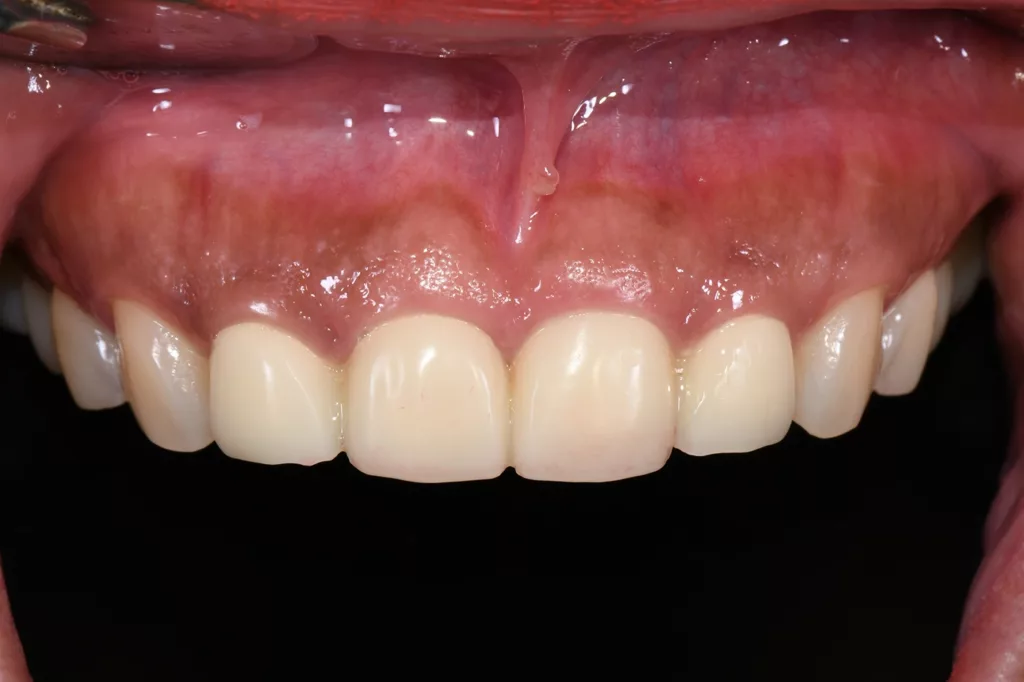

Die Kronen wurden in diesem Fall aus dem Material IPS e.max® ZirCAD Prime Esthetic von Ivoclar angefertigt. Die Transparenz des gewählten Zirkoniumdioxids ermöglichte die Fertigung dünner Kronen von 0,5 mm und gleichzeitig eine präzise Farbreproduktion ohne dicke Schichtung. Das Stumpfdesign wurde so gewählt, dass das Zirkoniumdioxid bis zur Inzisalkante reichte, um Schneidekantenfrakturen zu vermeiden. Die Schichtung erfolgte durch Auftragen von IPS e.max® Ceram Dentin-Pulver (OE1, OE2 und T1) auf das Grundgerüst (Abb. 57 bis 63).

Die fertigen Kronen nahmen die natürliche Zahnfarbe auf und überzeugten durch eine außergewöhnliche Transparenz. Obwohl die Präparationsrichtlinien für Frontzähne eine Kronendicke von 0,8 mm vorsehen, erfolgte aufgrund der Vitalität der Zähne eine möglichst geringe Präparation. Zwar erschienen die beiden mittleren Schneidezähne zunächst etwas kürzer, aber tatsächlich wurde die Länge der Kronen unter Berücksichtigung der aufgezeichneten Frontzahnführung der Patientin angemessen bestimmt. Durch diese Vorgehensweise lässt sich sicherstellen, dass die Kronen langlebig und geschützt sind (Abb. 64 bis 67).